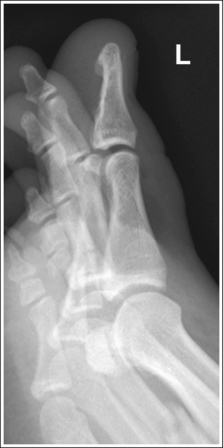

See Figures 6-5 and 6-6 and Box 6-3.

FIGURE 6-5 AP oblique toe projection with accurate positioning. DIP, Distal interphalangeal; MTP, metatarsophalangeal.

The digit(s) is rotated 45 degrees. Twice as much soft tissue width and more phalangeal and metatarsal concavity are present on the side of the digit rotated away from the IR.